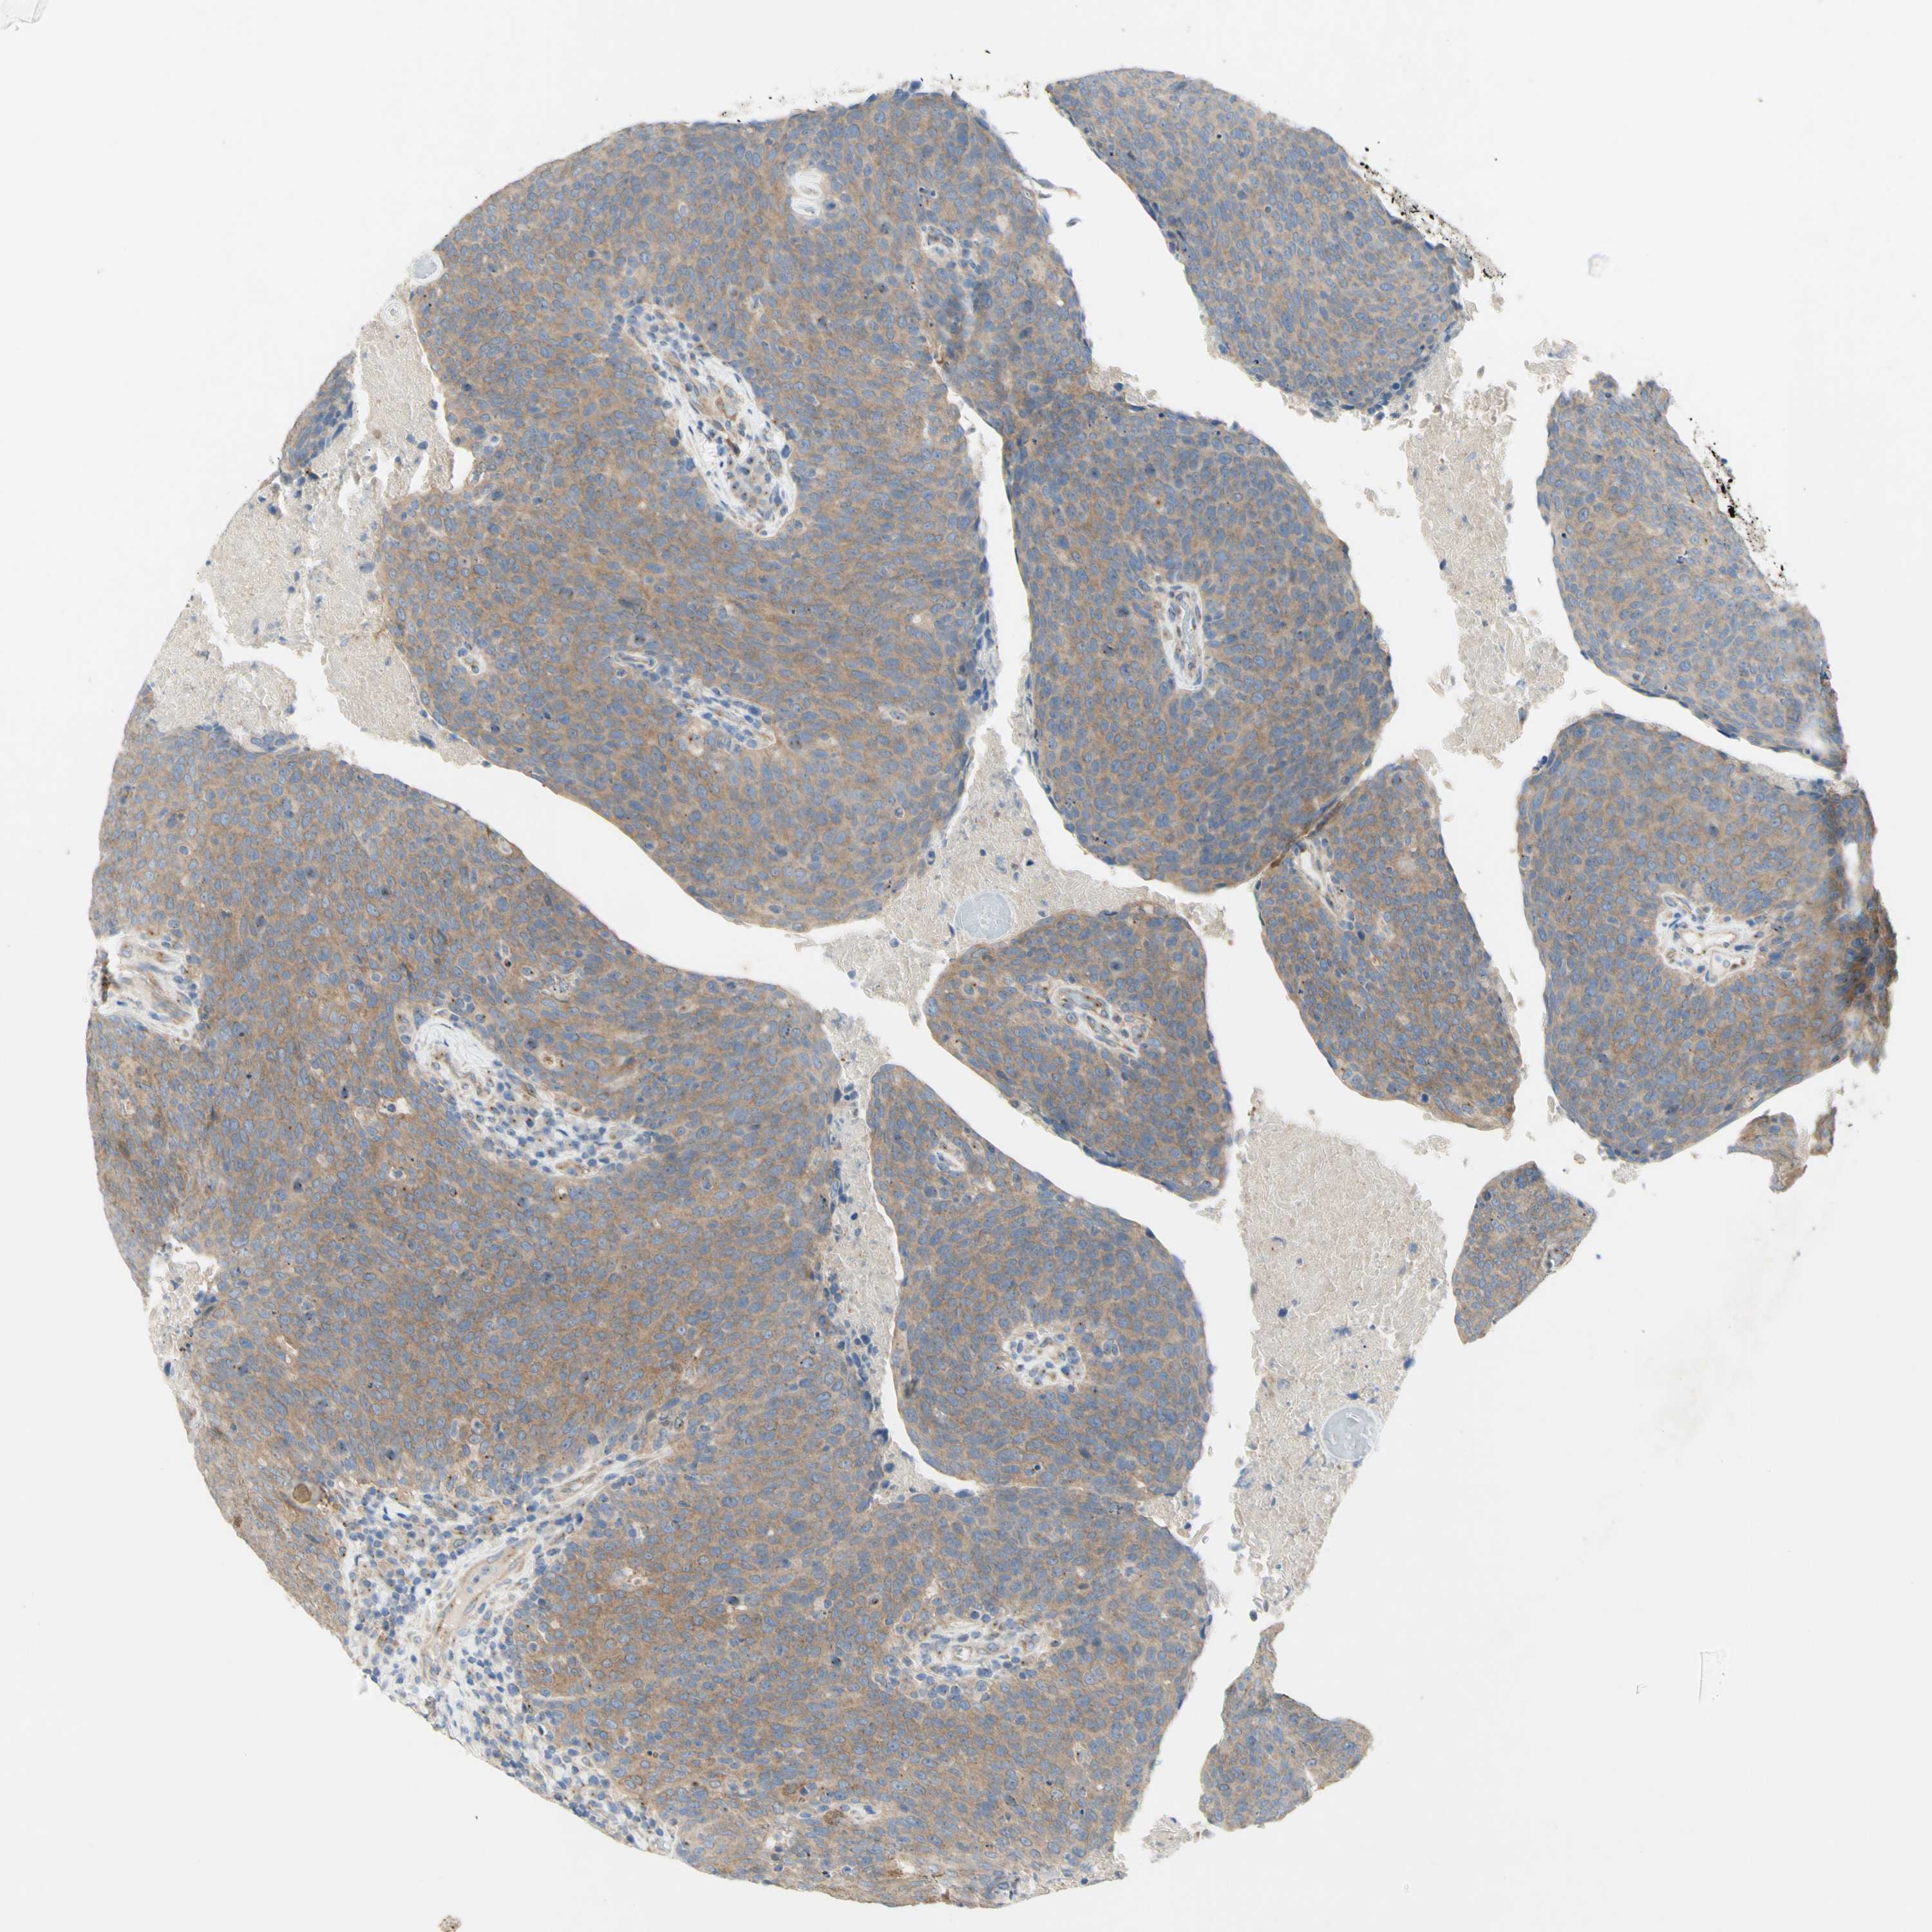

HEAD AND NECK CANCER - Protein expressioni

A mouse-over function shows sample information and annotation data. Click on an image to view it in a full screen mode. Samples can be filtered based on level of antibody staining by selecting one or several of the following categories: high, medium, low and not detected. The assay and annotation is described here.

Antibody stainingi

Antibody staining in the annotated cell types in the current human tissue is reported as not detected, low, medium, or high, based on conventional immunohistochemistry profiling in selected tissues. This score is based on the combination of the staining intensity and fraction of stained cells.

Each image is clickable and will lead to virtual microscopy that enables deeper exploration of all samples and also displays staining intensity scores, fraction scores and subcellular localization as well as patient and tissue information for each sample.

Antibody HPA003742

Antibody CAB010443

Staining

High

Medium

Low

Not detected

Intensity

Strong

Moderate

Weak

Negative

Quantity

>75%

75%-25%

<25%

None

Location

Nuclear

Cytoplasmic/membranous

Cytoplasmic/membranous,nuclear

Squamous cell carcinoma, NOS

Neoplasm, malignant, NOS

Adenocarcinoma, NOS